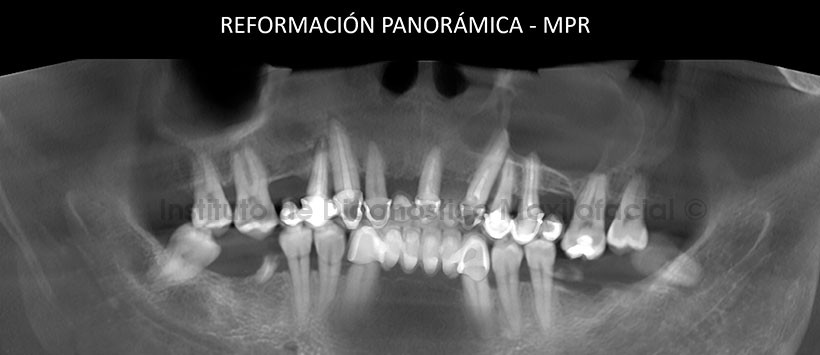

A la evaluación tomográfica se pudo obtener una reformación panorámica en “Proyección de Máxima Intensidad – MIP” (Figura 1) así como una reformación en “Reconstrucción Multiplanar – RMP” (Figura 2) en las cuales se aprecia una imagen isodenza en el maxilar superior a nivel del cuadrante dos.

Así mismo en los cortes axiales, se aprecia que dicha entidad consta de límites definidos y bordes parcialmente corticalizados, que a su vez presenta un contenido isodenso. Esta lesión también ocasiona la expansion de ambas tablas óseas (palatina y vestibular) comprometiendo estructuras como la pared anterior y medial de seno maxilar y parte del conducto nasopalatino. (Figura 3)

En los cortes transaxiales (Figura 4) y tangensiales (Figura 5), podemos apreciar que esta lesión se extiende desde mesilla de la pieza 23 hasta mesilla de la pieza 28, siendo las piezas 23, 24, 25 y 27 las que están comprometidas con esta lesión al perder la lámina dura en zona periapical y presentando una reabsorción radicular externa muy leve en el tercio apical. También se puede apreciar un engrosamiento de la mucosa de seno maxilar adyacente a la lesión y una expansión de la tabla ósea palatina y parte del paladar duro de ese mismo lado.